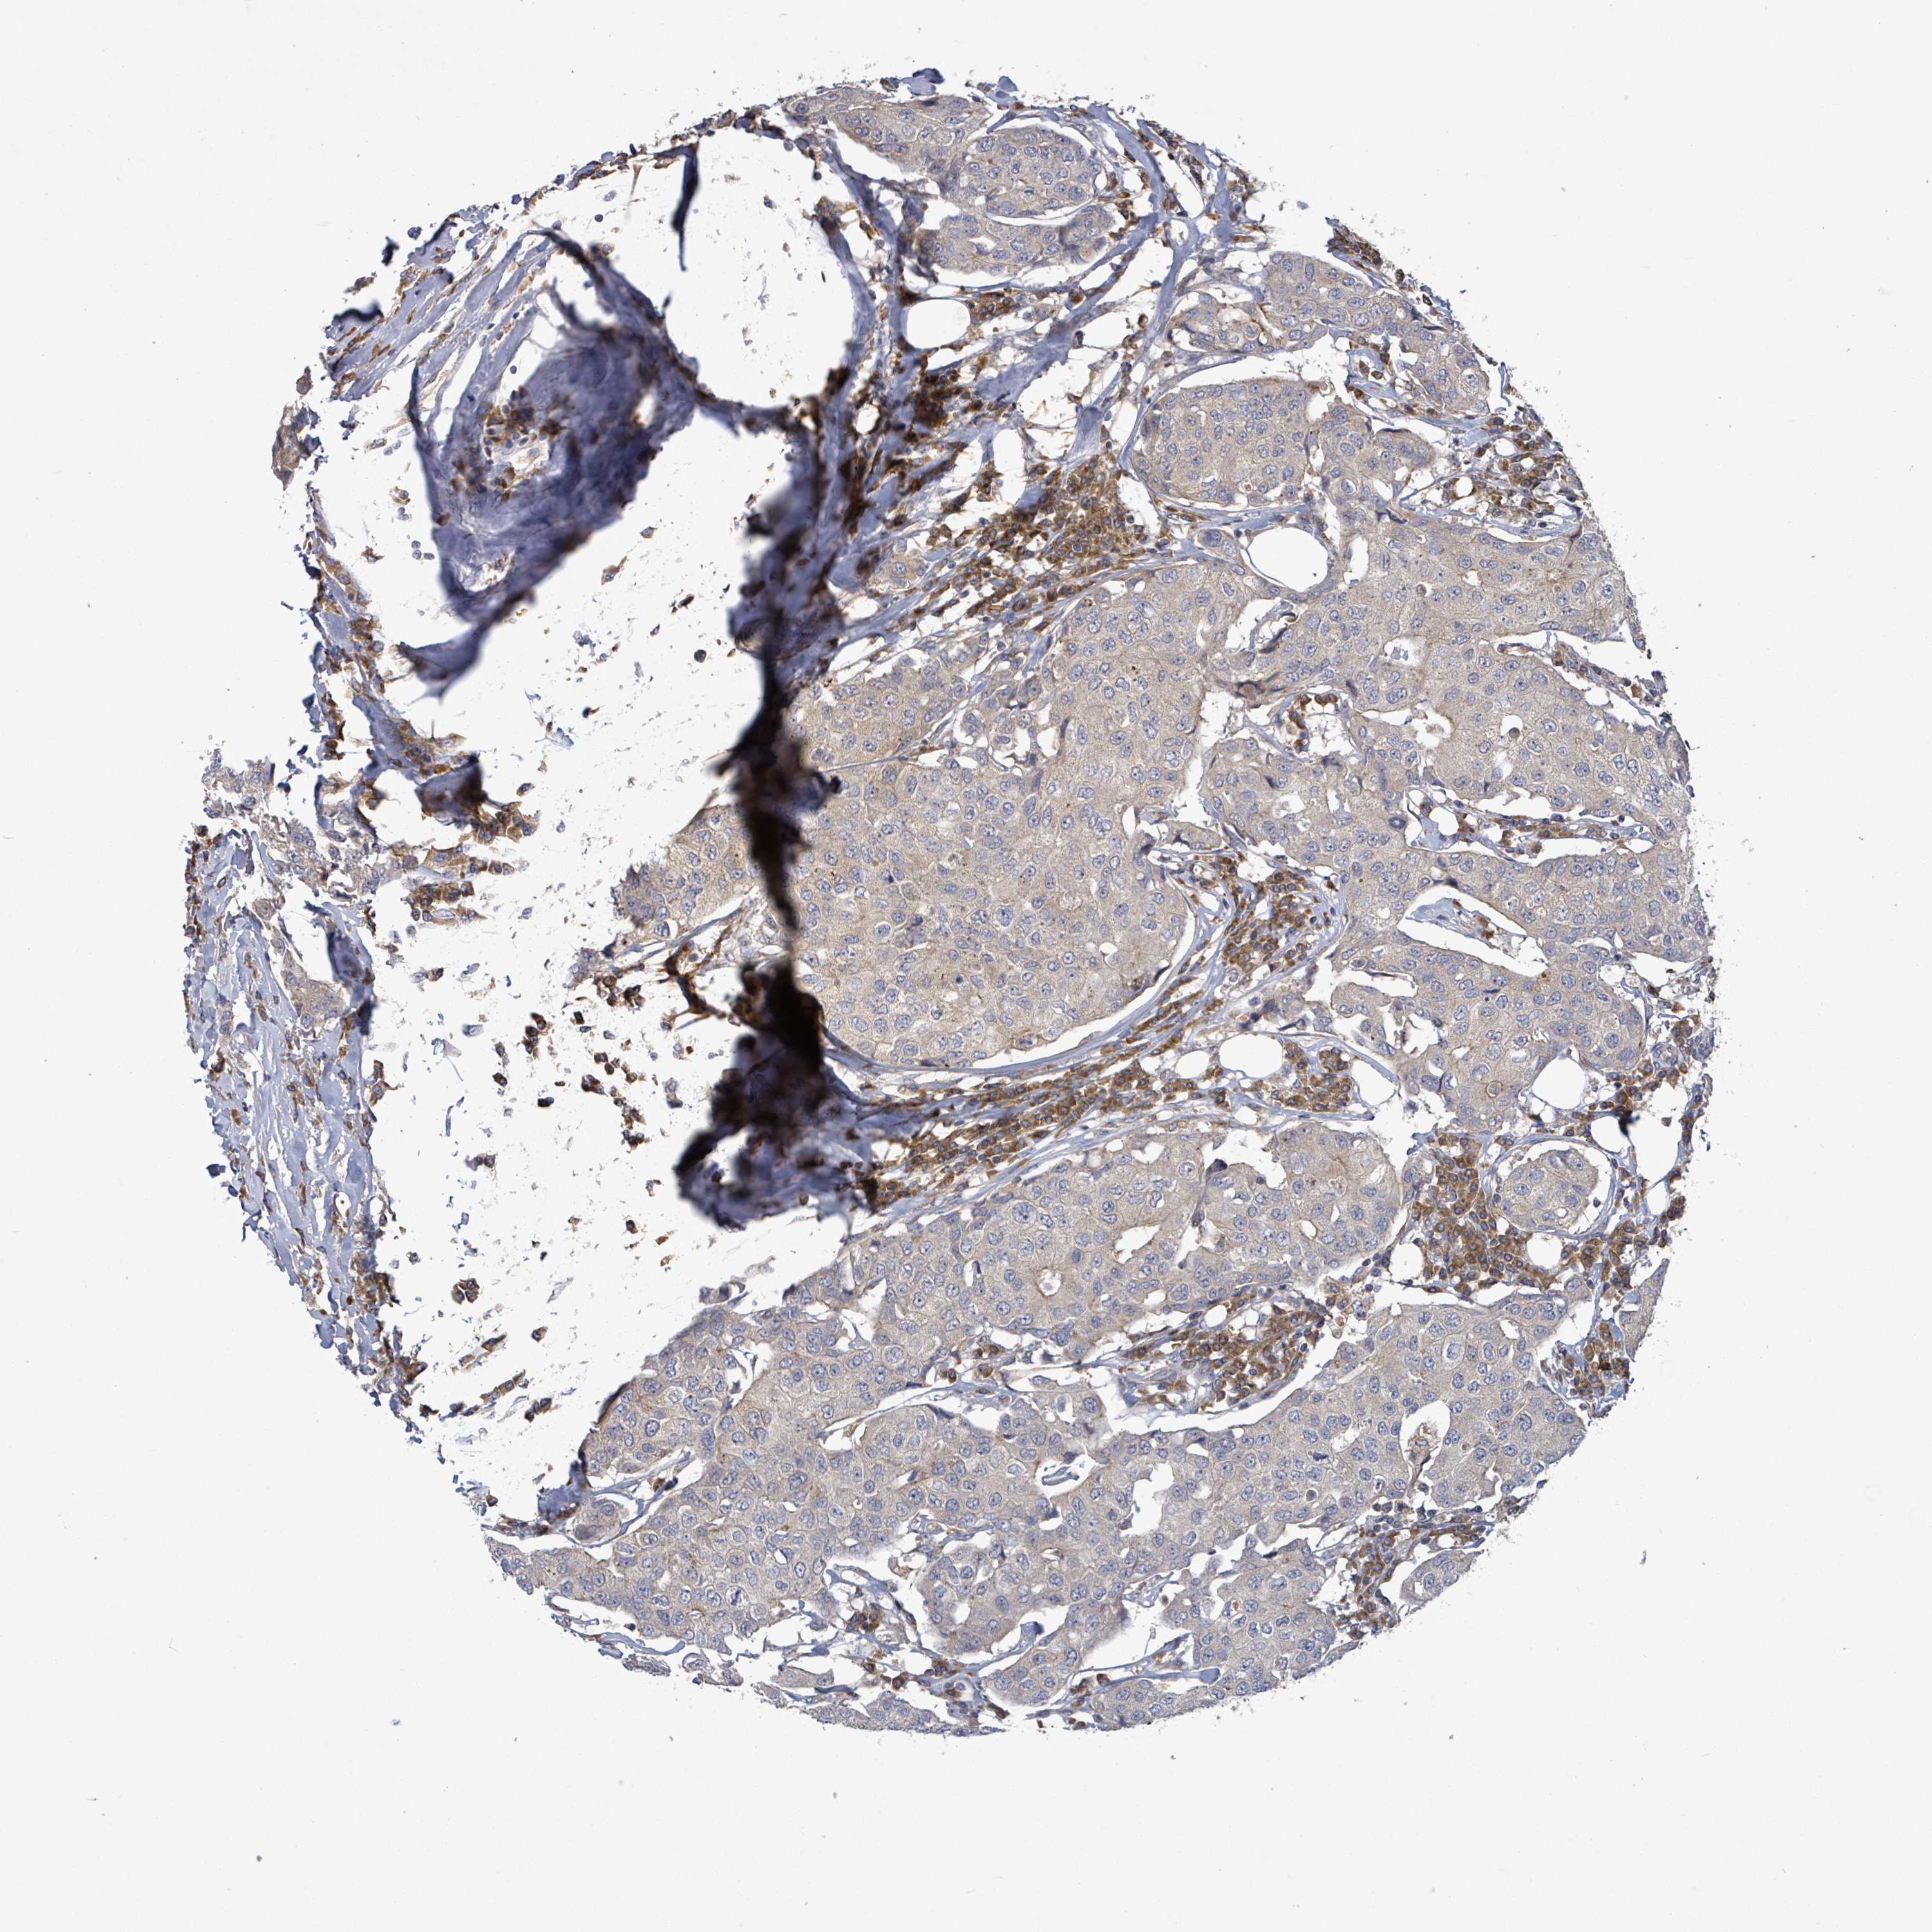

BRCA TCGA BRCA VALIDATION PROTEIN EXPRESSION

ANTIBODIES

AND

VALIDATION